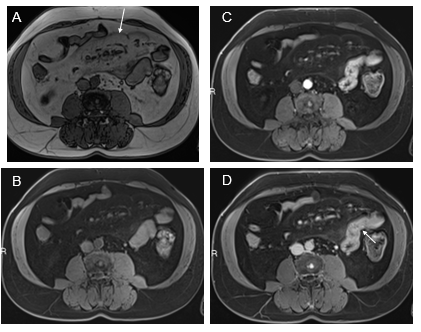

Esophagus: The esophagus of all upper digestive tract segments is the most commonly involved in the SIS, even in conditions that should predilect the jejunum, such as IBS. The most common appearance is mild inflammation. We have not seen examples of moderately severe or severe disease, and usually, enhancement on arterial images is normal, and the appreciation of inflammation is based on the increased enhancement on venous phase images. As the esophagus is in a fixed location and transverse images show a nice doughnut configuration, abnormal enhancement is most readily performed in this segment (Figure 1). Moderately severe to severe disease, most commonly, we have observed in conditions of infection such as candidiasis.

Figure 1 Axial T1-weighted GRE images. In-phase (A) and out-of-phase (B), exhibit signal drop of liver on out-of-phase images consistent with moderate steatosis. Moderately severely increased distal esophagus enhancement is well appreciated in the interstitial phase (arrow, D). The increased enhancement is suboptimal in the arterial phase images (C).